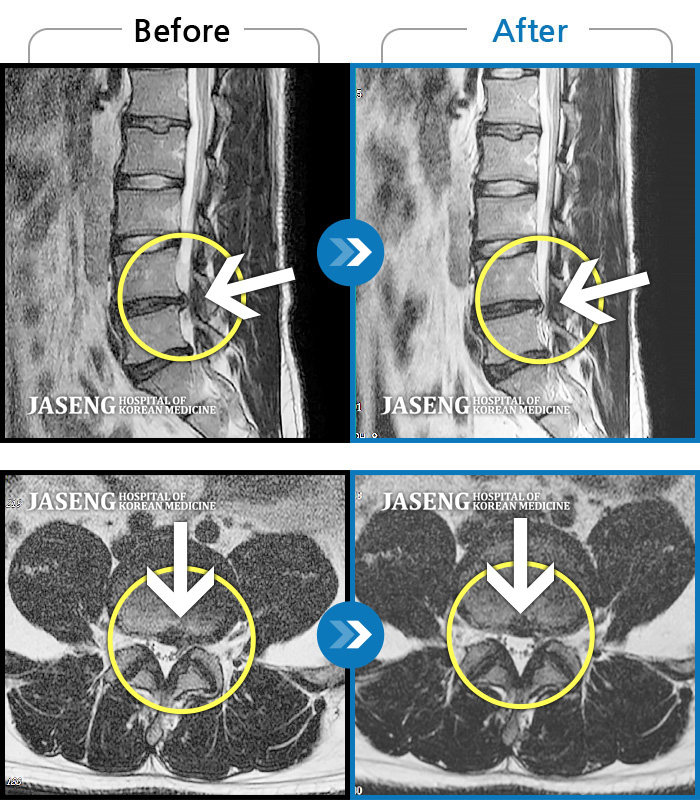

허리디스크

인천 · 강아현 원장

좌측 허리 통증 및 골반 통증이 심하여 걷는 것도 힘든 상태로 내원하셨습니다.

촬영시기

2024.05.08 ~ 2025.11.12

2025.11.14